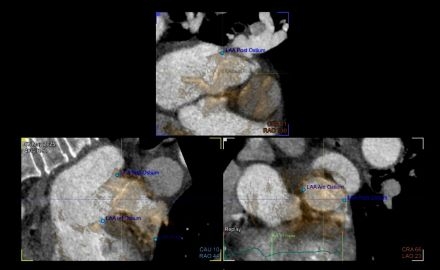

How to Watch a Watchman: Fused Cardiac Imaging for Left Atrial Appendage Closure

Atrial fibrillation (AF) is the most common sustained arrhythmia and is associated with an increased risk for thromboembolic stroke. Anatomically, the left atrial appendage (LAA) is recognized as the most common source of thrombus formation in patients with AF. Life-long anticoagulation is often needed to mitigate stroke risk. However, this requires strict patient adherence and increases the risk of bleeding. Left atrial appendage occlusion (LAAO) devices have been utilized to mitigate stroke risk while allowing for discontinuation of anticoagulation. Accurate visualization and measurement of the appendage is critical to achieve successful LAAO. Multiple imaging modalities have been studied for device sizing and implantation including intraoperative transesophageal echocardiography (TEE) and preprocedural planning with cardiac computed tomography (CT). CT has been shown to provide more detailed visualization of the LAA compared to TEE. Advancements in cardiac imaging allow for fusion of CT with TEE which may further improve procedural outcomes.

This study evaluated LAAO devices implanted using preoperative CT fused with intraoperative TEE (CT-TEE fusion) compared to those implanted with TEE without fused imaging. Key outcomes included procedure duration, quantity of LAAO devices used intraoperatively, incidence of adverse events, and 45-day leak.